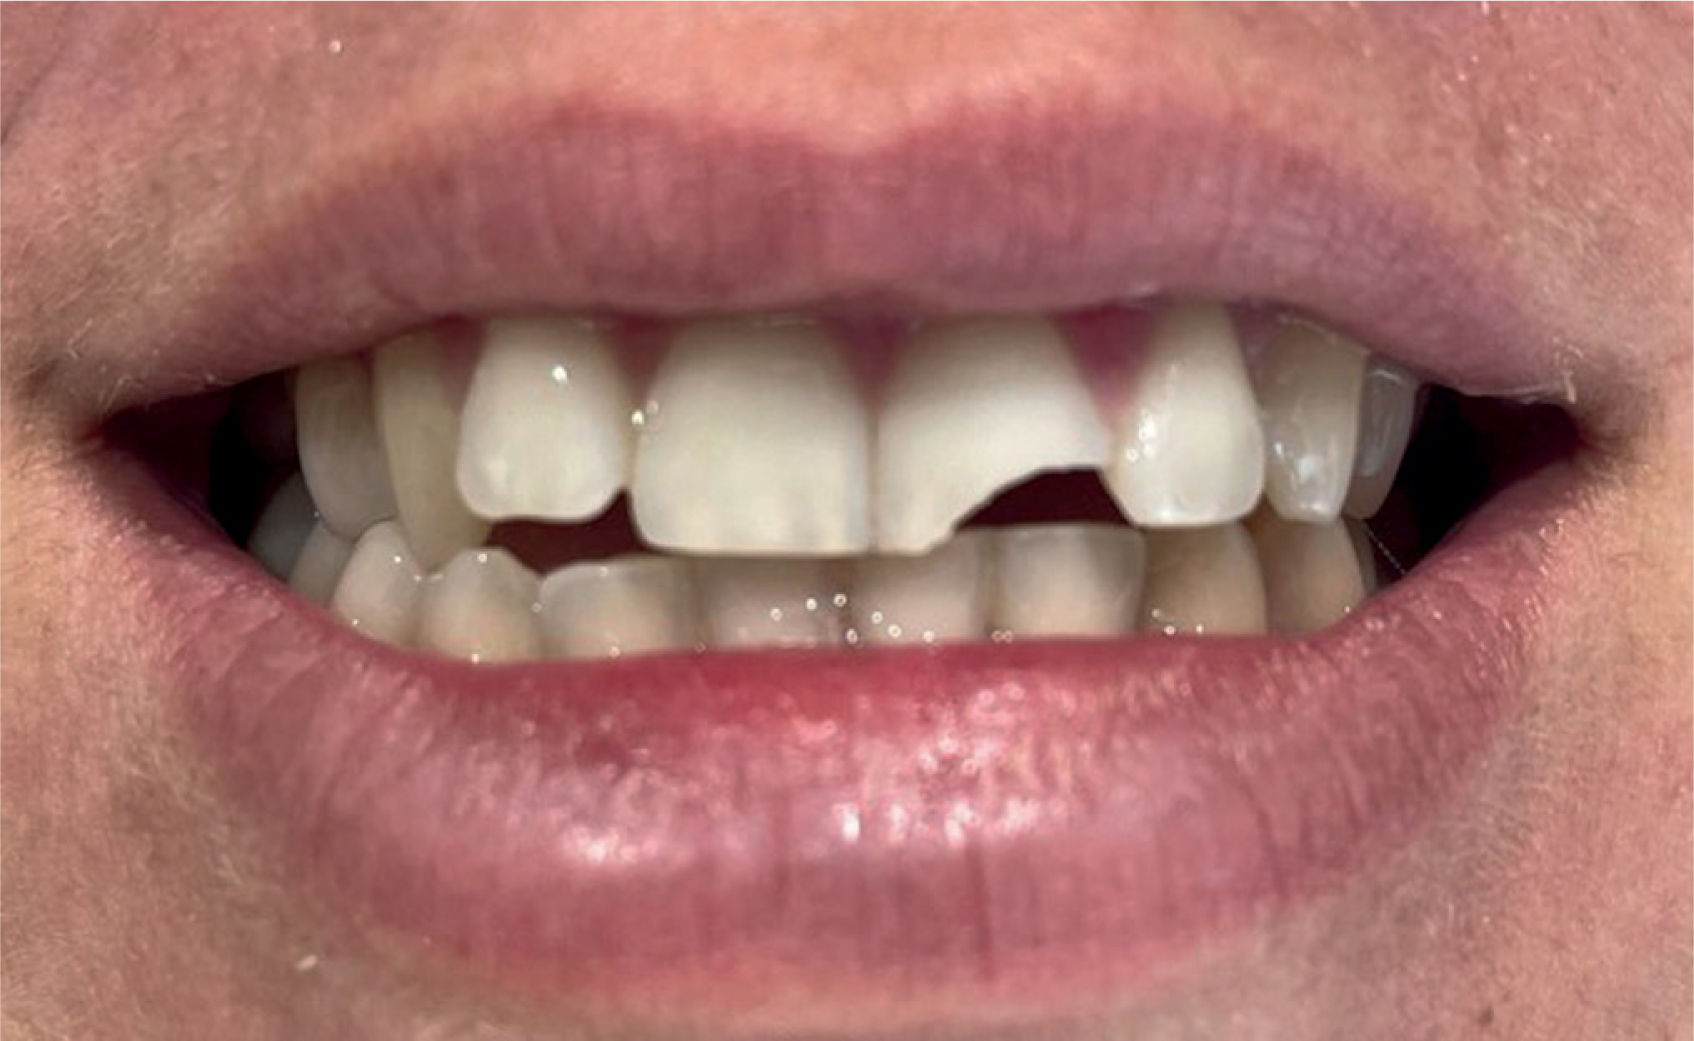

Traumatismo dentalLas lesiones dentales por traumatismo son frecuentes, especialmente en deportes de contacto y en paciente pediátrico. Según la OMS un 20% de la población mundial sufrirá un traumatismo dental a lo largo de la vida7.

Los incisivos centrales son los dientes más frecuentemente afectados (fig. 11).

FracturaFractura tipo I: se limita al esmalte. No requiere tratamiento urgente.

Fractura tipo II: afecta a la dentina. Sensibilidad a los cambios térmicos. Se considera una urgencia odontológica.

Fractura tipo III: se extiende a la pulpa. Se considera una urgencia odontológica.

En la figura 12 se pueden ver los diferentes tipos de fracturas dentales según el grado de afectación.